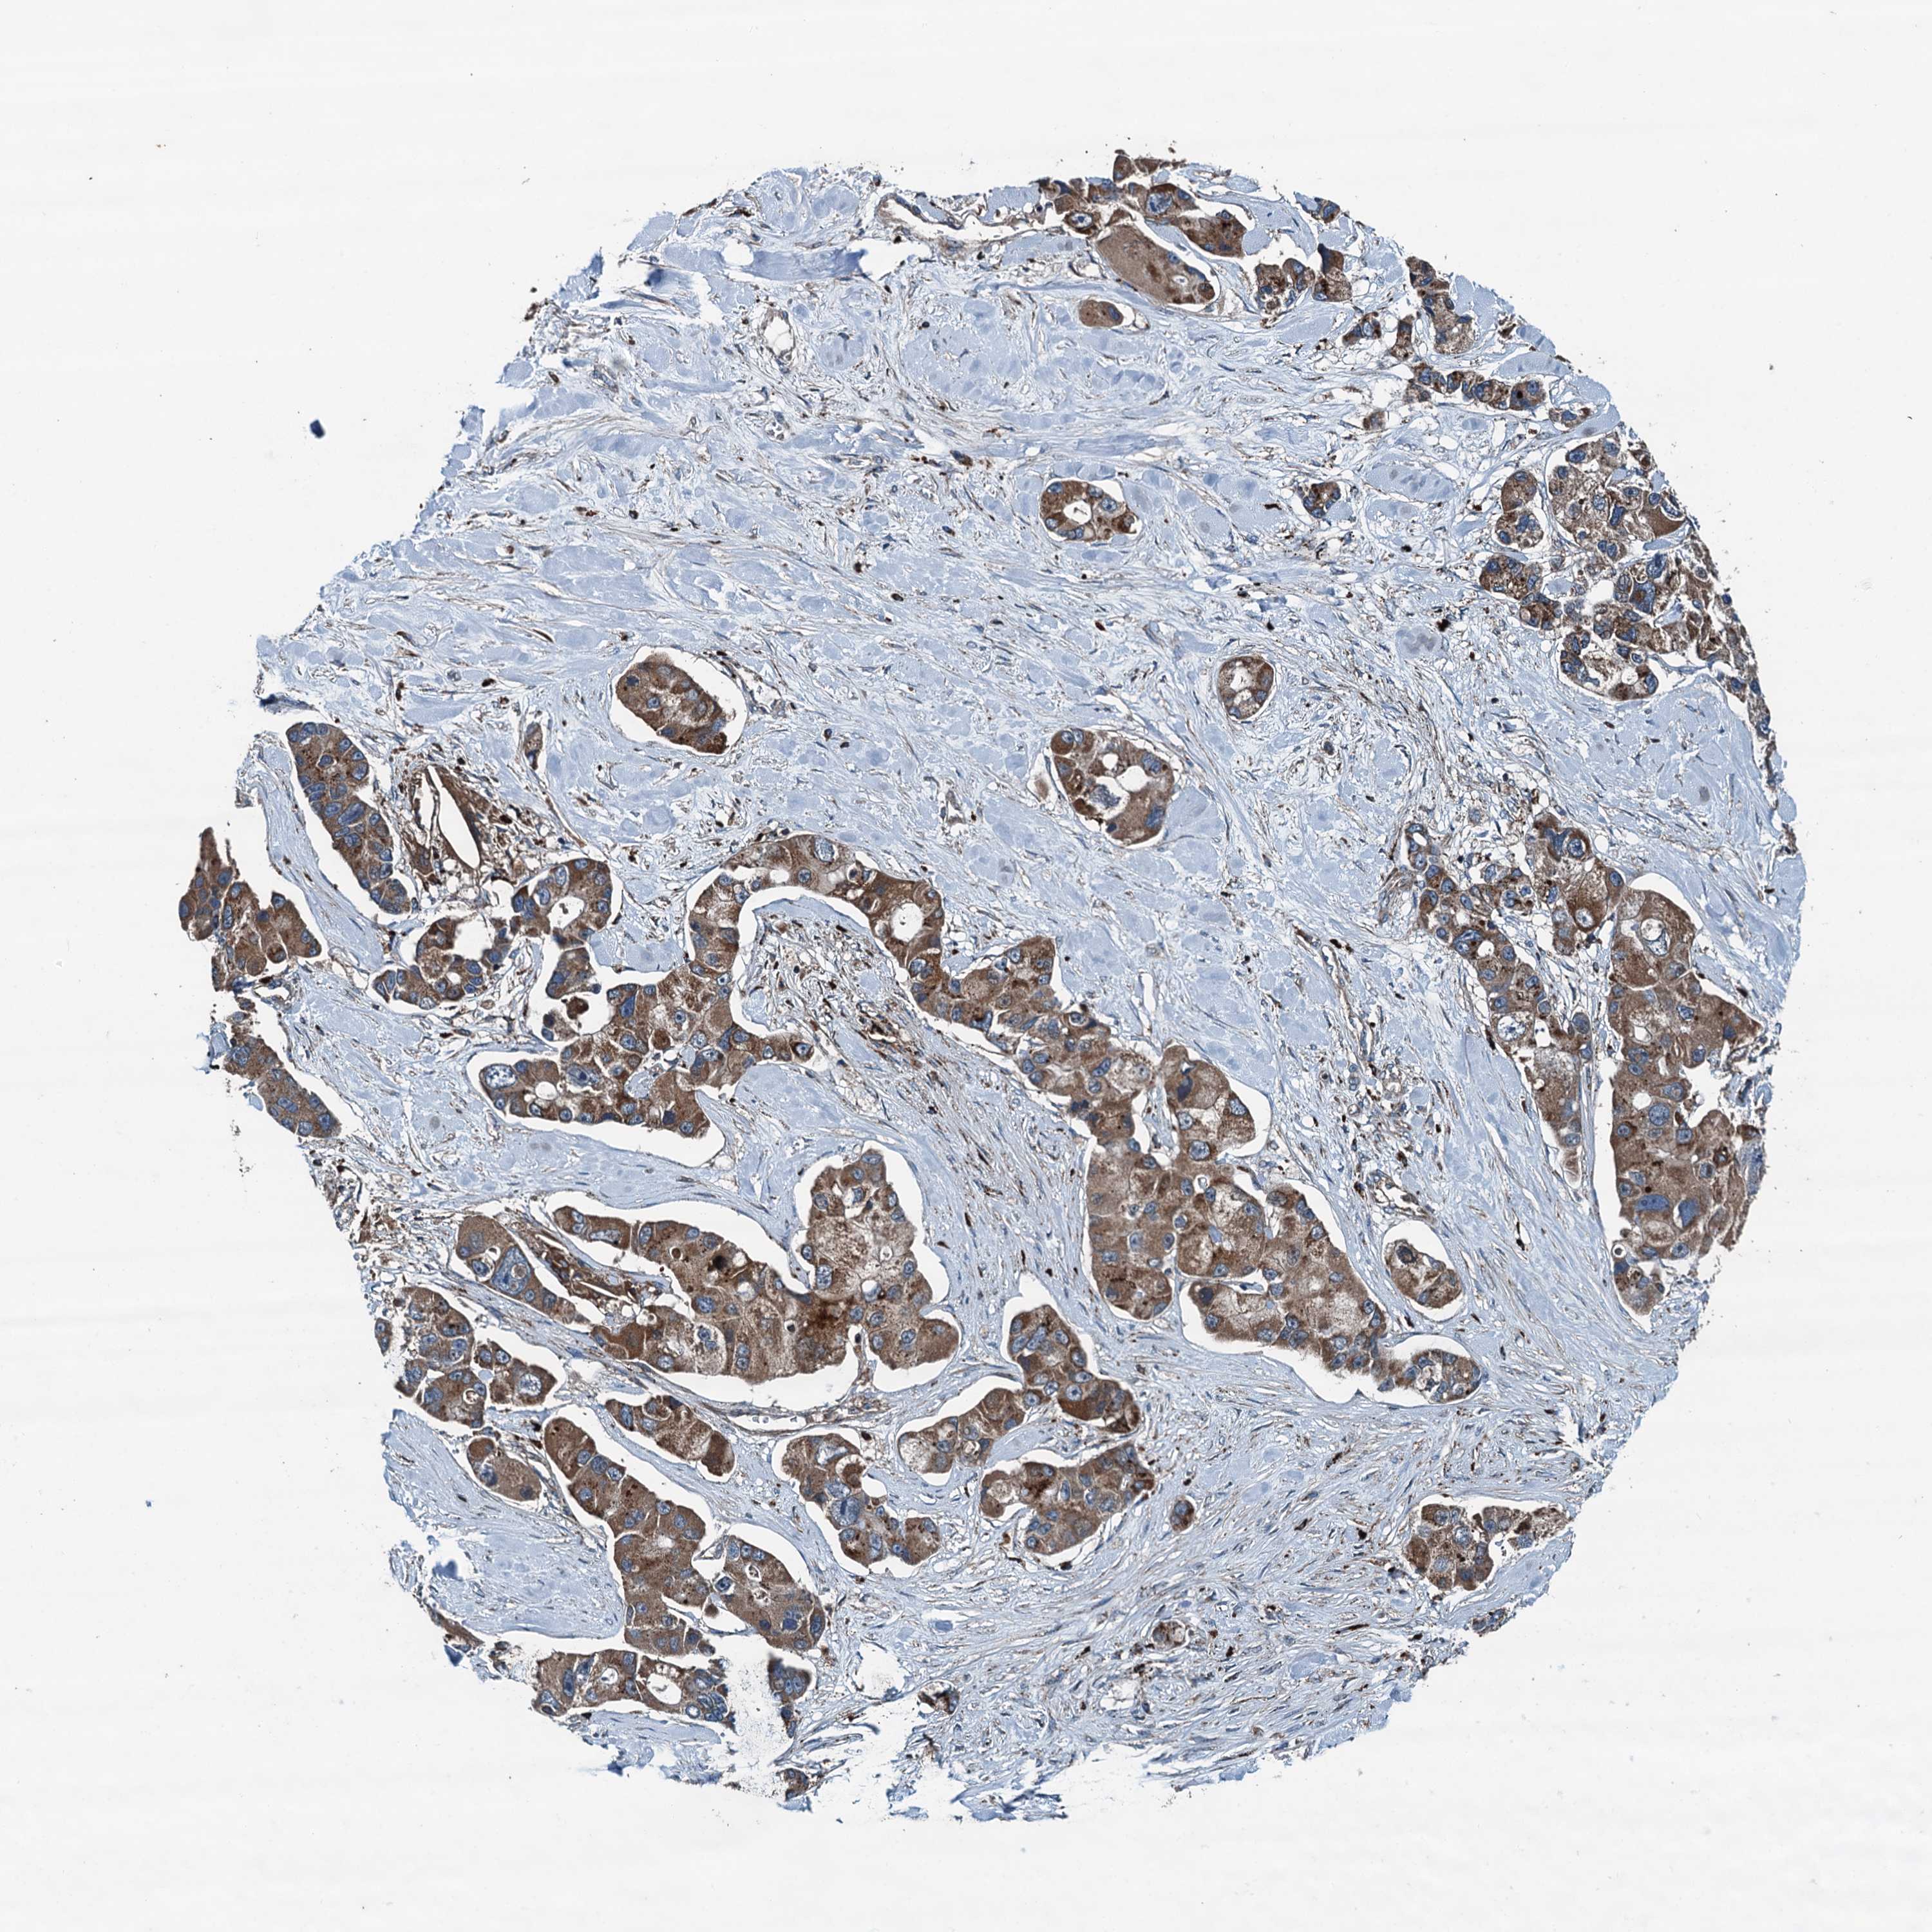

CANCER LUNG CANCER Show tissue menu

Lung cancer

Human cancer

Lung adenocarcinoma